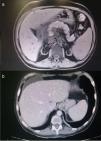

Exámenes complementarios: Analítica: glucosa 106mg/dl, urea 163mg/dl, creatinina 3.74mg/dl, amilasa 631UI/l, lipasa 1027U/l, GOT 53U/l, GPT 68U/l, GGT 196U/l, FA 80U/l, LDH 676U/l, calcio 6.3mg/dl, PCR 1.07mg/l, sodio, potasio y coagulación normales. Hemograma: Hb 12.1g/dl, Hto 38.5%, VCM 99fl, leucocitos 10.050μl con 8.610μl de neutrófilos, plaquetas 100.000μl. PCR CMV negativo. Carga viral VHC 17600000UI/ml. Autoinmunidad y marcadores tumorales normales (tabla 1). TAC de abdomen y RMN del páncreas y colangio-RM de vías biliares: compatibles con pancreatitis aguda intersticial con bajo índice de severidad (Figura 2 a y b). Eco-endoscopia normal. La paciente cumplía criterios analíticos y de imagen de pancreatitis aguda intersticial leve según criterios de Atlanta. Cultivos de exudados de MMII negativos para bacterias y hongos.